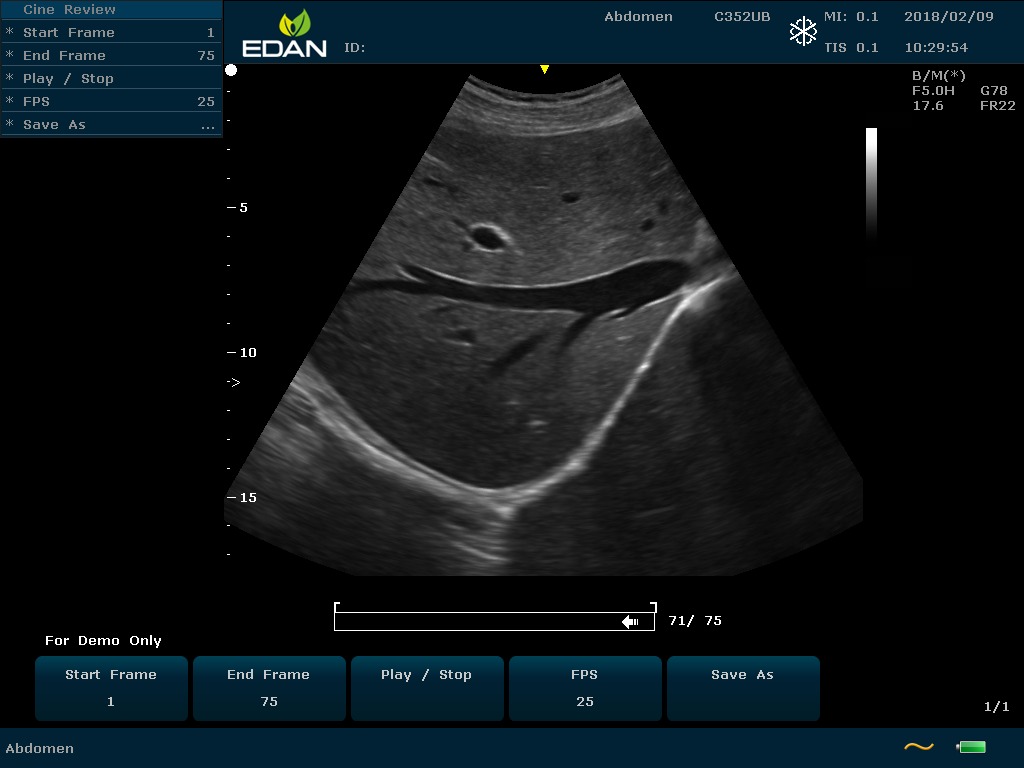

Особенность U60 Edan — расширенное применение. Ультразвуковой аппарат рекомендован для абдоминальных исследований, гинекологии и акушерства, кардиологии, педиатрии, урологии, изучения малых органов, сосудов. Для U60 Edan используются конвексные, линейные, фазированные и внутриполостные датчики.

Передовые технологии позволяют повысить качество визуализации в несколько раз. УЗИ-аппарат U60 Edan отличается возможностью быстрой настройки визуализации. Специальные функции позволяют моментально отображать данные за счет быстрой оптимизации параметров. Режимы визуализации: B-mode, M-mode, Color Doppler, Power Doppler Imaging, Pulsed Wave Doppler, Continuous Doppler.